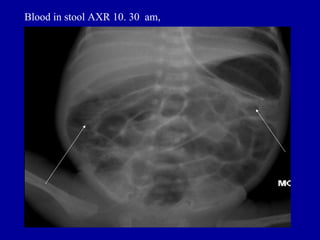

Blood in stool AXR 10. 30 am,

Blood in stoolAXR 10. 30 am,